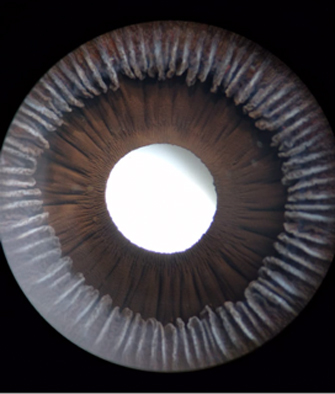

Iris

Cara posterior de Iris: incluye Iris y Cuerpo Ciliar, Foto tomada de globo ocular de banco de ojos.